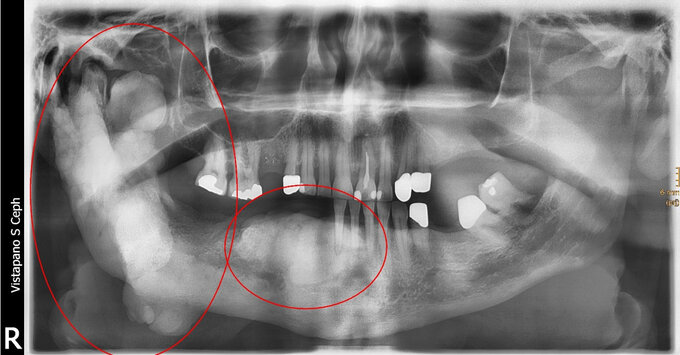

Es werden zwei Hauptformen unterschieden: Konventionelle, multizystische Ameloblastome sind die häufigsten Ameloblastome und treten zu 80% im hinteren Teil des Unterkiefers auf. Ihr Wachstumsmuster ist mehrkammrig, weshalb es oft als "seifenblasenartig" beschrieben wird. Dadurch kommt es auch zu Satellitenbildungen und zur Ausdehnung bis in die Markräume des Kiefers. Durch ihr expansives, infiltratives Wachstum sind Resorptionen von Zahnwurzeln möglich. Von multizystischen Ameloblastomen unterscheiden sich unizystische Ameloblastome. Bei diesen kommt es seltener zum Anlösen von Zahnwurzeln, vielmehr neigen diese zur Verdrängung von Zähnen. Sie wachsen als unilokuläre Knochenauflösung, was die Entfernung einfacher gestalten kann. Die radikale chirurgische Resektion ist bei beiden Formen die Therapie der Wahl. Aufgrund der hohen Rezidivgefahr bei unvollständiger Entfernung sollte bei der Resektion ein Sicherheitsabstand in Betracht gezogen werden. Postoperative sind regelmäßige klinische und röntgenologische Verlaufskontrollen wichtig.

Die odontogene Keratozyste wurde historisch zunächst als Zyste klassifiziert; 2005 wurde sie aufgrund ihres invasiven und aggressivem Wachstums sowie der hohen Rezidivrate umklassifiziert bzw. umbenannt und als „keratozystisch odontogener Tumor“ (KOT) zu den Kopf-Hals-Tumoren gezählt. Seit 2017 wird sie als „Odontogene Keratozyste“ wieder den odontogenen Kieferzysten zugeordnet. Häufig ist das erste Symptom einer Keratozyste die Kippung oder Lockerung von Zähnen. Dabei bleiben die in die Zyste hineinragenden Zähne jedoch immer vital. Keratozysten können uni- und multiloklulär vor allem im hinteren Unterkiefer auftreten. Keratozysten können auch im Rahmen von Syndromen auftreten, insbesondere dem Gorlin-Goltz-Syndrom, bei dem neben multiplen Keratozysten auch bösartige Hauttumore (Basaliome) und Veränderungen im Skelettknochen auftreten können. Im radiologischen Befund finden sich „girlandenförmige“ Knochenauflösungen (=Osteolysen). Die Therapie der Wahl ist eine Zystektomie, also die vollständige Entfernung der Zyste. Ein Problem stellen die häufig auftretenden Satellitenzysten dar, von denen eine hohe Rezidivgefahr ausgeht. Deshalb sollten regelmäßige postoperative klinische und röntgenologische Verlaufskontrollen durchgeführt werden, um eine frühzeitige Erkennung von Rückfällen zu ermöglichen.

Der häufigste gutartige odontogene Tumor ist das Odontom. Es tritt gehäuft zwischen dem 10. und 20. Lebensjahr auf. Odontome sind entwicklungsbedingte Fehlbildungen (Harmatome), die aus versprengtem Keimgewebe entstehen. Ihr Wachstum ist nicht autonom, sondern verläuft mit dem Wachstum des umgebenden Gewebes parallel. Invasives oder verdrängendes Wachstum ist daher eher untypisch. Odontome fallen häufig durch sog. retinierte, d.h. im Kiefer „steckenbleibende“ Zähne auf. Sie können ein Durchbruchshindernis für diese Zähne darstellen und somit die physiologische Einstellung der bleibenden Zähne in den Zahnbogen verhindern. Odontome bestehen aus einer bindegewebigen Kapsel in der sich Anteile von Schmelz, Dentin und Zement findet. Es werden zwei Formen von Odontomen unterschieden: Zusammengesetzte Odontome finden sich meist im vorderen Oberkiefer und sind besser organisiert. Sie bestehen oft aus kleinen, zahnähnlichen Gebilden, die sich diagnostisch häufig bereits im OPG (Orthopantomogramm) einzeln erkennen lassen. Komplexe Odontome finden sich vermehrt im hinteren Unterkiefer und zeigen sich unorganisiert. Zahnstrukturen sind zwar vorhanden aber unregelmäßig angeordnet, wodurch eher wolkige Verschattungen erkennbar sind. Als Therapie ist die chirurgische Entfernung des Odontoms einschließlich der Bindegewebskapsel anzustreben. Nach der Entfernung ist die Prognose für einen spontanen Durchbruch eines retinierten Zahnes sehr gut. Durch die Entfernung können auch lokale Probleme wie das Verschieben von Nachbarzähnen oder beginnende Wurzelresorptionen vermieden werden.